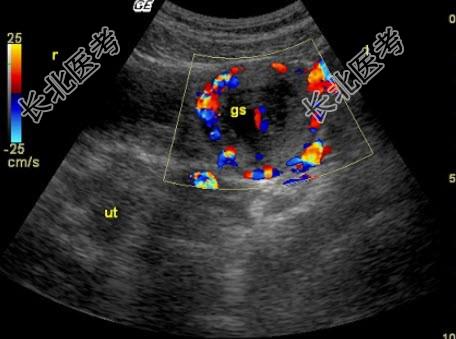

- 单项选择题女性,22岁, 停经40天,尿HCG阳性。超声检查见图, 最可能诊断为( )

A、炎性包块

B、黄体囊肿

C、正常声像图

D、宫外孕

E、畸胎瘤